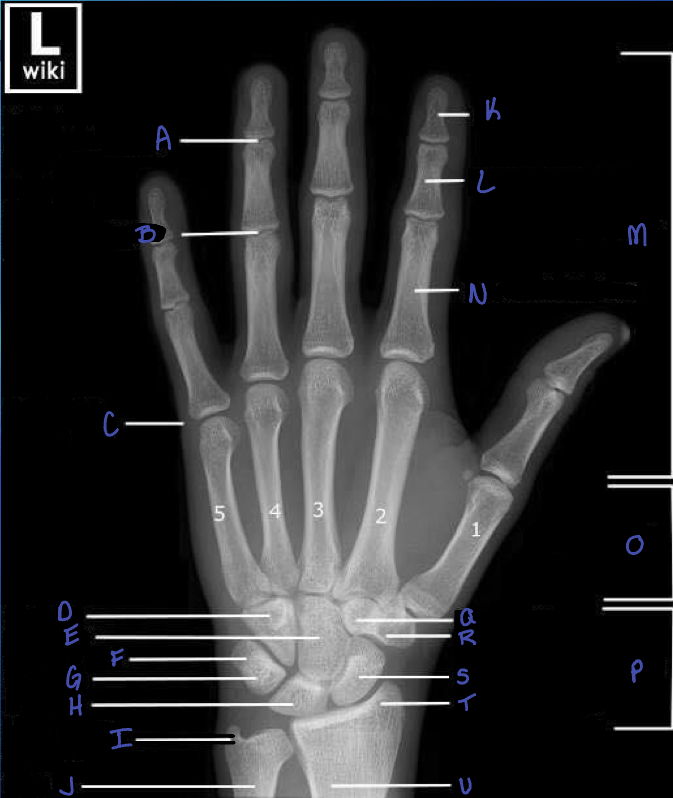

13

What is A?

A

distal interphalangeal joint

14

What is B?

proximal interphalangeal joint

15

What is C?

metacarpophalangeal joint

16

What is D?

hamate b

17

What is E?

capitate b

18

What is F?

triquetrium b.

19

What is G?

pisiform

20

What is H?

lunate b.

21

What is i?

ulna styloid process

22

What is J?

ulna

23

What is K?

distal phalanx

24

What is L?

middle phalanx

What is M?

what is N?

proximal phalanx

27

metacarpals

What is P?

29

trapezoid b.

30

trapezium b.

31

scaphoid b.

32

radial styloid process

33

radius